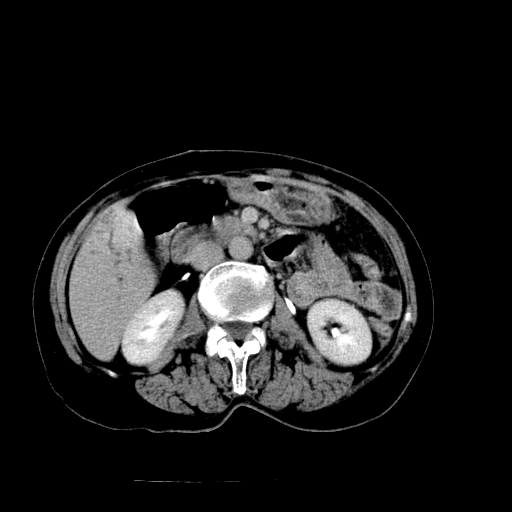

以下是引用卜一在2009-4-7 5:06:00的发言:[br]左右肝内胆管结石伴扩张合并胆系感染;不除外胆管细胞癌可能。支持! [br] [br]

以下是引用随光逐影在2009-4-7 8:21:00的发言:[br]肝内外胆管多发性结石并肝内外胆管扩张;胆系感染。